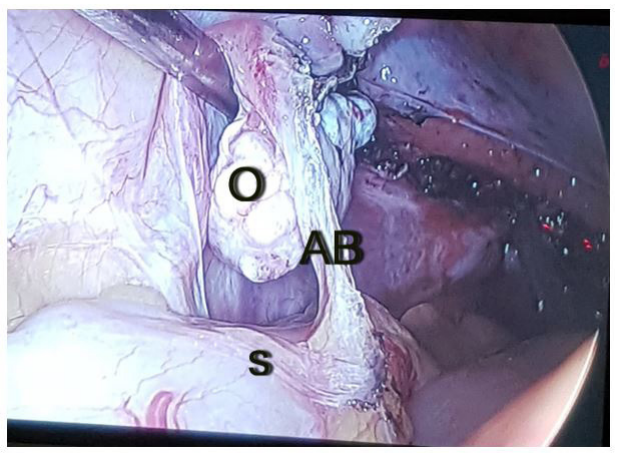

The intraabdominal pressure was maintained at 8 — 10mm for check laparoscopy and 12 — 14 mm of Hg for operative laparoscopy procedures. In CL, blood clots, if any were aspirated through the suction cannula. Bleeder if any was coagulated. Remnant pelvic adhesion if any was lysed (Figure 1). Endometriotic spot if any was coagulated. Remnant endometriotic nodules, broad ligament fibroid, and adnexal pathologies if any were excised. The excised specimens were removed through the vaginal vault. A laparoscopic bipolar sealer-shearer or cutter was used for laparoscopic procedures. Laparoscopic lavage was done. Then, the laparoscopy was concluded and the vault was closed.

| Figure 1: Shows a remnant adhesion band (AB) between the left ovary(O) and the sigmoid colon(S) following VH, and was detected during PHCL |